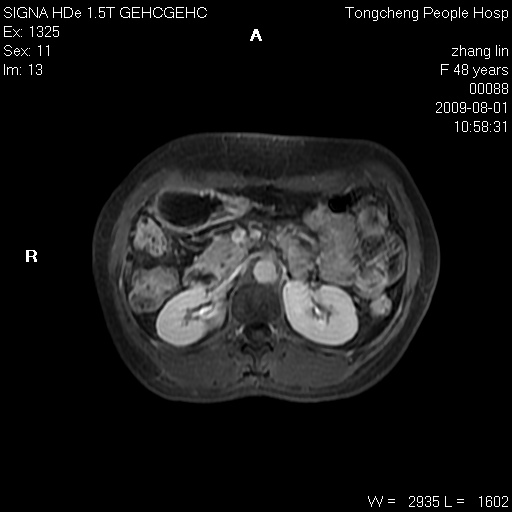

女,48岁。健康体检,彩超发现右肾占位性病变。平素健康。

临床诊断:右肾占位性病变,性质待定(囊肿?肿瘤?)。

上中腹部mr平扫+增强扫描,图像如下:

右肾上极见一类圆形病灶,t1wi呈等信号t2wi呈等高混杂信号,三期增强无强化,边界清---考虑囊肿出血。

同反相位均表现为等信号,病变无强化,考虑含蛋白的囊肿可能,弥散加权相或许有些帮助,